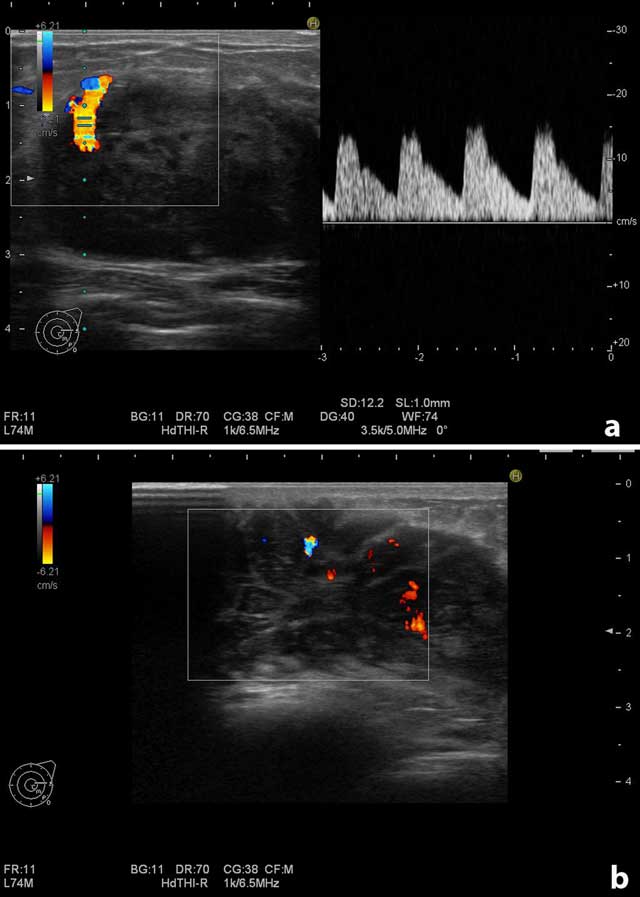

On physical examination, there were multiple palpable mass lesions in the lower quadrant in both breasts, with the largest being 4.5 cm in diameter in the right breast. There were no palpable axillary mass and no breast discharge or retraction of the areola. The ultrasonographic examination (Hitachi-Preius, 13–8 MHz) revealed multiple lobulated, hypoechoic, solid masses with circumscribed contours (Figure 1a). The largest mass measured 4.5 × 2.7 cm (Figure 1b). Power Doppler examination demonstrated increased vascularity in the masses (Figure 2a and b).

Figure 2

Doppler examination of the largest mass on the right breast. (a) Increased vascularity at the contours of the mass. (b) Increased vascularity in the internal part of the mass.